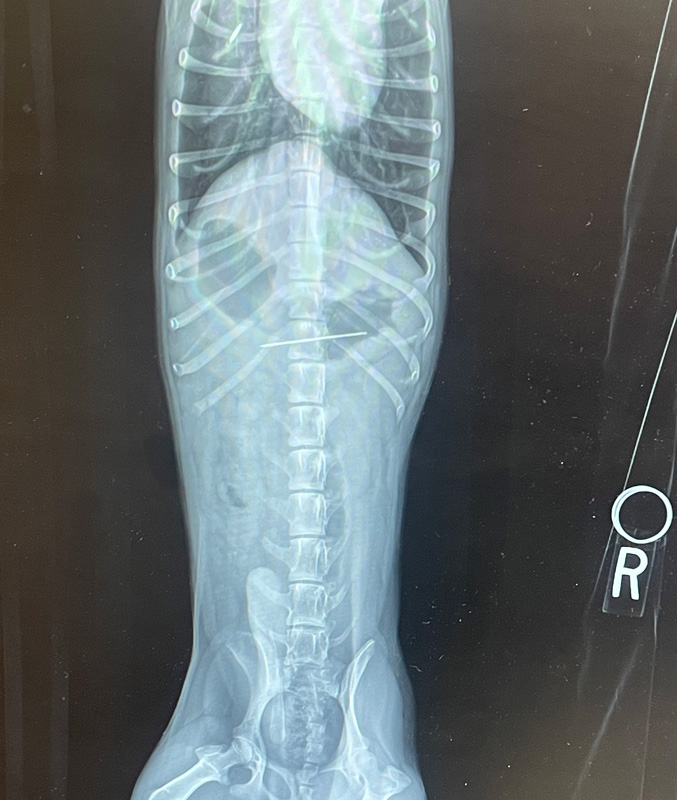

“He’s just an idiot,” Sydney tells me on the phone. “He’s very cute, but so stupid.” She says this fondly, but I understand. Ziggy is a year and a half old. His nicknames are Piggy or Hoover. Because he will eat anything that falls on the floor. Anything. The first late night call was last October. Xenia had been making felt leaves for a DIY Poison Ivy Halloween costume, using an extra felt piece as a makeshift needle holder. She must have knocked it onto the floor without noticing. Later that evening, they found the felt piece in Ziggy’s crate. Without the needle.

“Could he have swallowed the needle?” Syd called me, concerned. I have seen several cats swallow needles. Usually it is because they are playing with the attached thread. I have surgically removed one needle from a cat’s intestines, one from where it migrated through the cat’s esophagus to poke out behind the shoulder, one that was deeply embedded in the roof of the cat’s mouth. I also saw one that surprisingly passed all the way through the cat’s digestive tract uneventfully, coming out in the feces. I have seen a boxer puppy who swallowed a closed box of pins that opened in his stomach. He survived after his veterinarian surgically removed them all. I have seen dogs ingest safety razors, broken glass, popsicle sticks, rocks, toys, super balls — but never a needle.

“How is he acting?” I asked. Ziggy was feeling completely fine. Was it possible the needle had fallen out of the felt and was somewhere on the floor? Maybe, but search as they might, they couldn’t find it. I advised feeding him high-fiber foods like squishy white bread, or canned asparagus, which work well to wad up around sharp objects, then to call their local veterinarian in the morning. In my heart of hearts, I doubted the dog had swallowed the needle.

I was wrong. Two days later, after Ziggy began vomiting, he went to the veterinarian, where they were able to remove the needle from his stomach using an endoscope. Ziggy made a full recovery, and I felt remiss that I had not sent them to their veterinarian immediately.